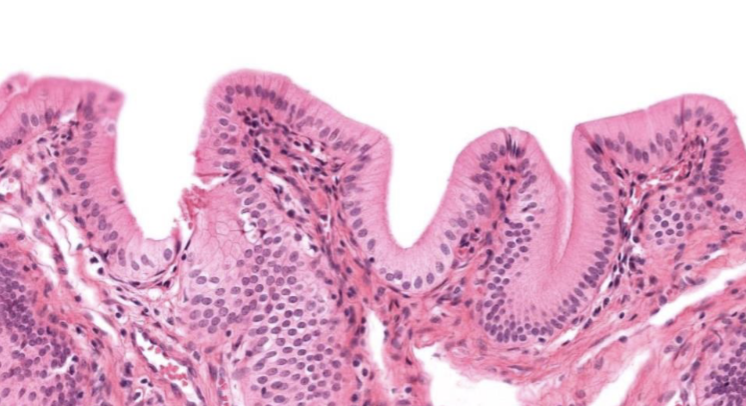

Forma de sus células

plano

Número de estratos

simple

Indique órgano o sistema que posee este epitelio

alveolo